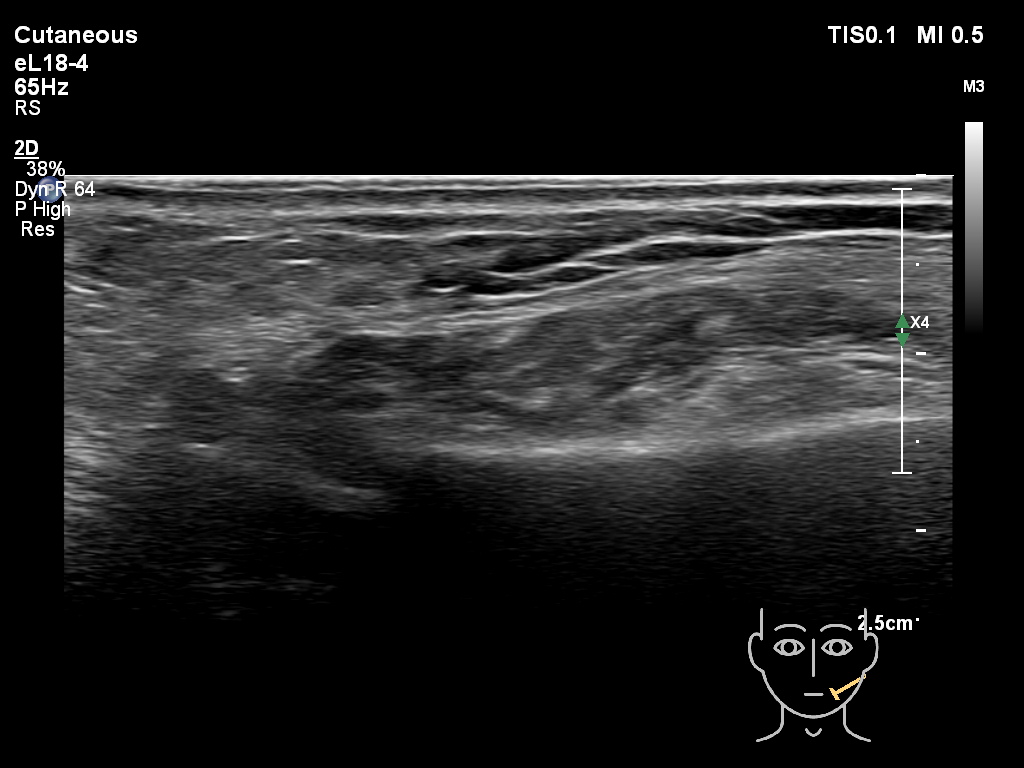

Fillers

Fillers

Draw in the second image below where the fillers are located. To check if your answer is correct, swipe the first image to the right.

HAca 2a

-